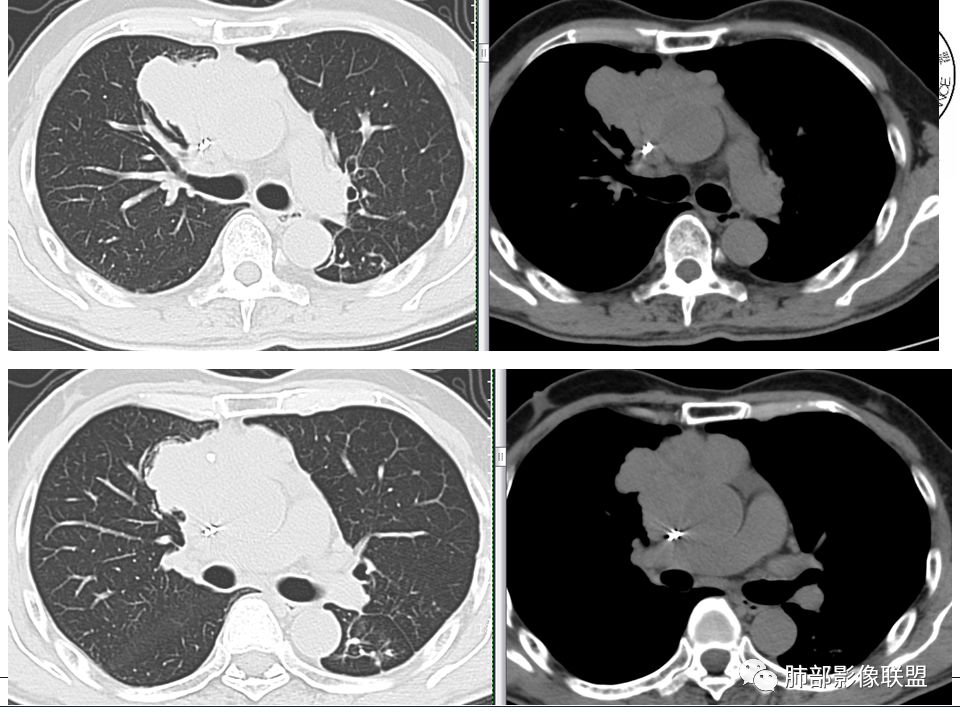

胸腺上皮性肿瘤包括胸腺瘤和胸腺癌,而前者是前纵隔最常见的肿瘤;现目前多采用1999年WHO胸腺肿瘤组织学分型,按病理类型可分为6个亚型,即A、AB、B1、B2、B3及胸腺癌,又根据肿瘤的侵袭性和复发性将胸腺瘤分为低危型胸腺瘤(A、AB、B1)、高危型胸腺瘤(B2、B3)和胸腺癌;“良性胸腺瘤”的概念不符合医学实践,即使A型胸腺瘤也存在复发和转移的风险,所以现在胸腺瘤均为恶性肿瘤,都具有潜在复发和转移可能,只是恶性程度不一。

因为有时候影像不好鉴别胸腺瘤的亚型,尤其少数B3型跟胸腺癌鉴别仍存在困难;那如何大致辨别低危型胸腺瘤、高危型胸腺瘤跟胸腺癌呢?我们主要从肿瘤的轮廓形态、肿瘤内部的成份(囊变坏死、钙化、纤维分隔等)、周围组织侵犯情况(胸膜、血管、心包、肺、膈神经)、有无纵隔淋巴结转移及远处转移来综合分析,为疾病的治疗及预后是有重要价值的。

1.轮廓形态:

包膜完整、边缘光滑、规则---低位胸腺瘤;

边界不清、边缘不规则、分叶---高危胸腺瘤和胸膜癌;

2.内部成分:

a.多数密度均匀,少见囊变坏死,见纤维分隔影及钙化---多见于低位胸腺瘤,而且纤维分隔影以AB型显著, 实质性钙化多提示AB型及以上,A型钙化多发生于被膜钙化,呈蛋壳样;

b.密度不均匀,囊变坏死多见,纤维分隔影少见,有钙化---多见于高危胸腺瘤及胸腺癌以上,尤其大片囊变坏死多见于B1型以上胸腺瘤跟胸腺癌;钙化多见于肿瘤实质内,非边缘区,多发的泥沙样、微钙化及多形性钙化多见于B2、B3型;

(随着侵袭性的增强,纤维分隔影会逐渐减少)

3.周围及远处情况:

a. 纵隔脂肪线清晰,无胸膜、血管、心包及肺情况,罕见纵隔淋巴结肿大及远处血行转移--低危胸腺瘤

b. ①纵隔脂肪间隙模糊、胸膜、心包侵犯、膈肌受累--见于高危胸腺瘤及胸腺癌,但是心包侵犯多见于B3胸腺瘤跟胸腺癌

②纵隔大血管侵犯、肺转移、膈神经麻痹、淋巴结转移及远处血行转移---多见于胸腺癌,B3胸腺瘤罕见